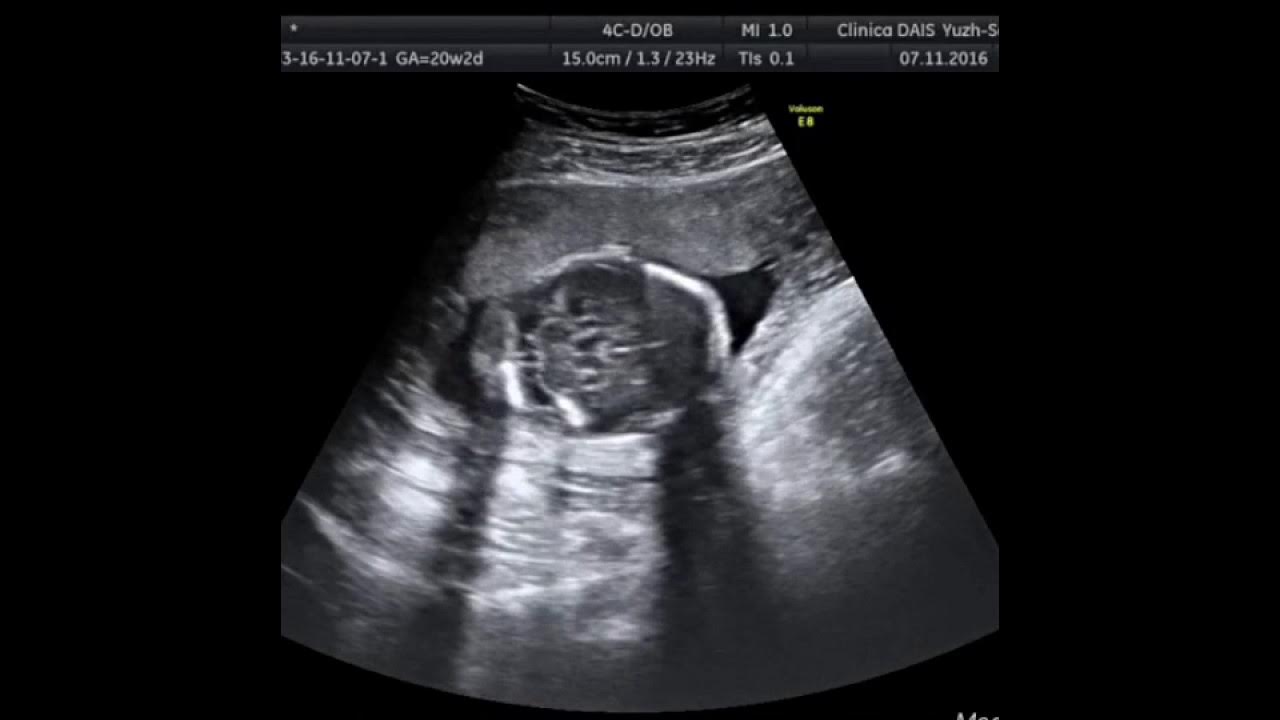

Определение пола 20 неделе ошибки